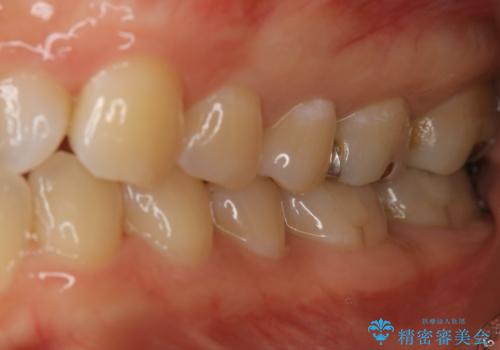

奥歯を白くしたい

- 左上6番の銀歯をセラミックにしたいと希望され来院された患者様です。

切削量を考慮し、セラミックインレーを選択しました。

銀歯を除去したところ虫歯が深かったので、CRを詰めた上で形態を整えています。